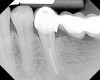

Figure 16  After initial positioning of the bone, keeping the tip of the laser in intimate contact with the root surface, a slight troughing of the bone was seen on radiographic examination.

Figure 16